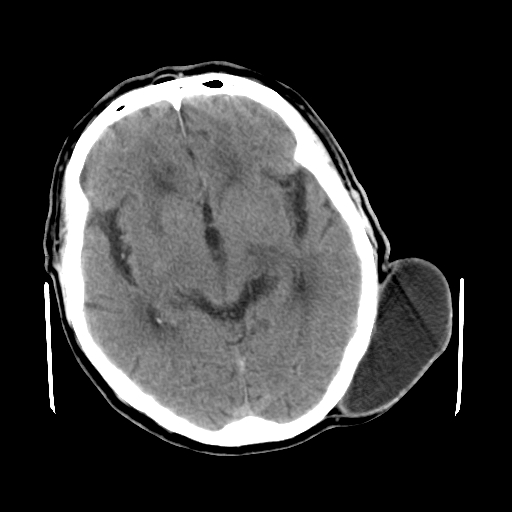

标题: CT25147:男,62岁,右侧肢体活动障碍不灵活三天。 [打印本页]

男,62岁,右侧肢体活动障碍不灵活三天,左侧头皮肿物十余年(ct值8hu)。

1)多发性腔隙性脑梗塞。2)脑白质病。3)脑萎缩。4)左侧枕顶部头皮下皮样囊肿,不排除脂肪瘤。

1)多发性腔隙性脑梗塞。2)脑白质病。3)脑萎缩。4)左侧枕顶部头皮下皮样囊肿或表皮样囊肿。